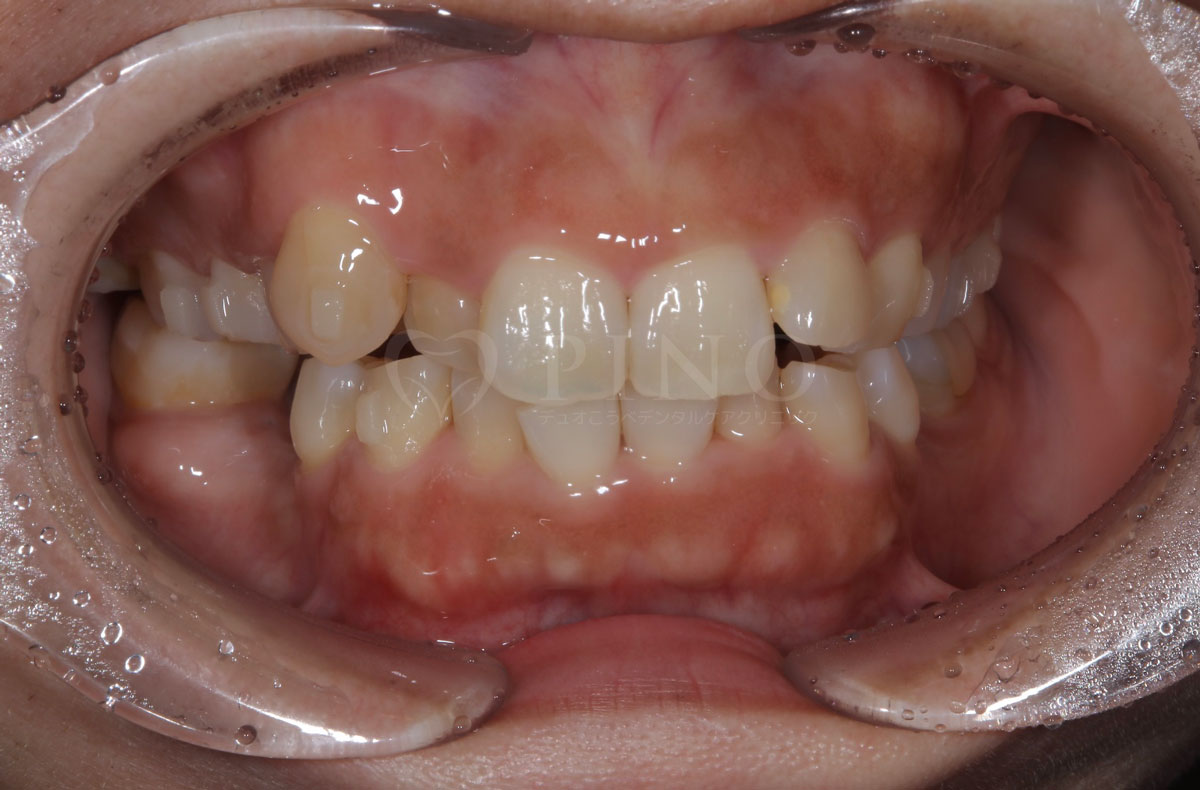

症例1:歯並びが気になる、歯がないところも治したい(50代女性)

主訴 歯並びが気になる、歯がないところも治したい 診断名 上顎前突、叢生、右下6欠損歯 治療方法 マウスピース全額矯正、インプラント 抜歯 あり 上2本 オルソパルス あり 治療期間 2年2ヶ月 費用 891,000円+インプラント400,000円 副作用・注意点 矯正後の後戻りを防ぐためリテーナーの使用が必要となる 備考 2年8ヶ月でインプラントも治療完了した -